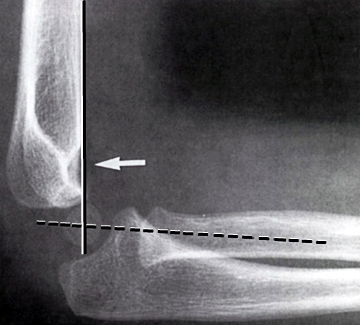

En linie gennem centrum af radius skal altid gå lige igennem capitulum humeri.

En linie langs forsiden af humerus går normalt igennem midterste 1/3 del af capitulum humeri, hvis capitulum ligger bagved skal der reponeres og osteosynteres i GA. Hos børn under 4 år tillades lidt større dislokation.